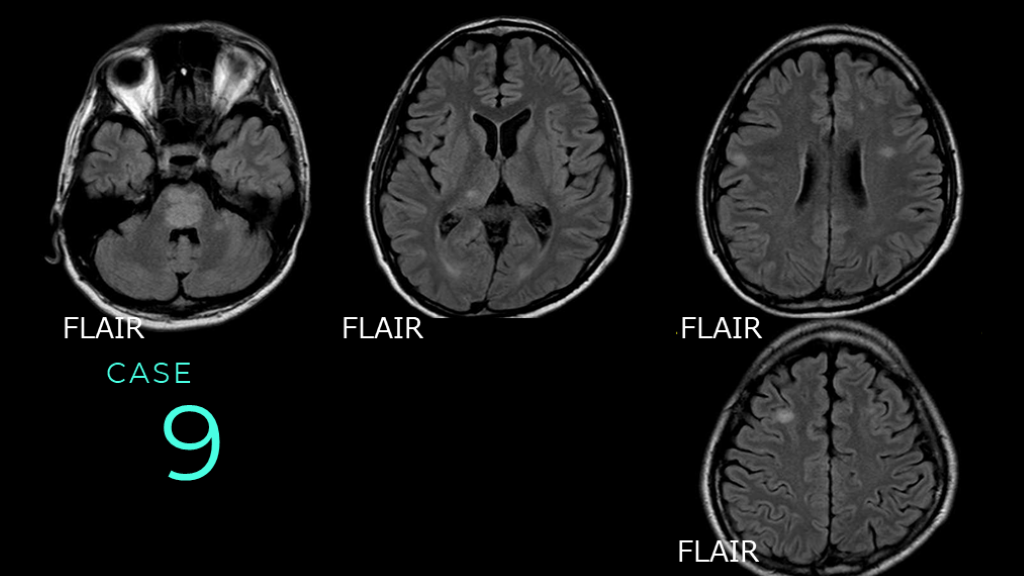

9 CASE FLAIR FLAIR FLAIR FLAIR

9 CASE FLAIRで高信号病変が散在している。脳幹、脳深部、前頭葉白質に斑状の高信号病変が認められる。

9 CASE コメント:ADEMの症例。これも1つ提示するならFLAIR、としてプレゼンする。一部皮質も含むが、白質病変主体である、というニュアンスを強調している。